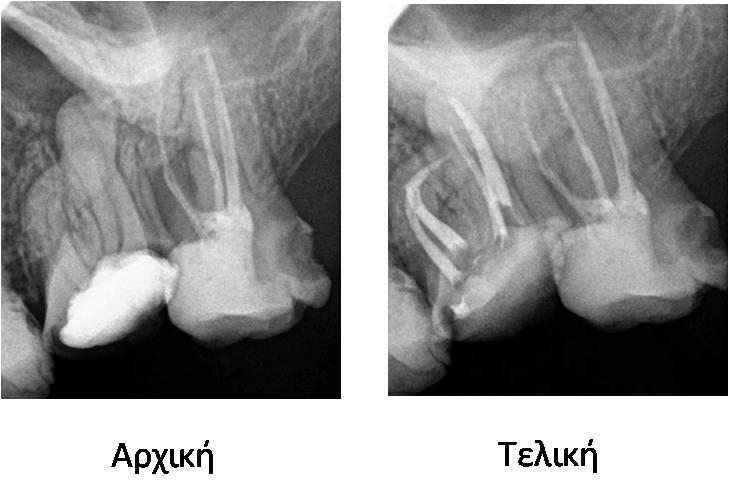

Περιστατικό 6

Περιστατικό 6

Ενδοδοντική θεραπεία σε δόντι με έντονη κάμψη ρίζας